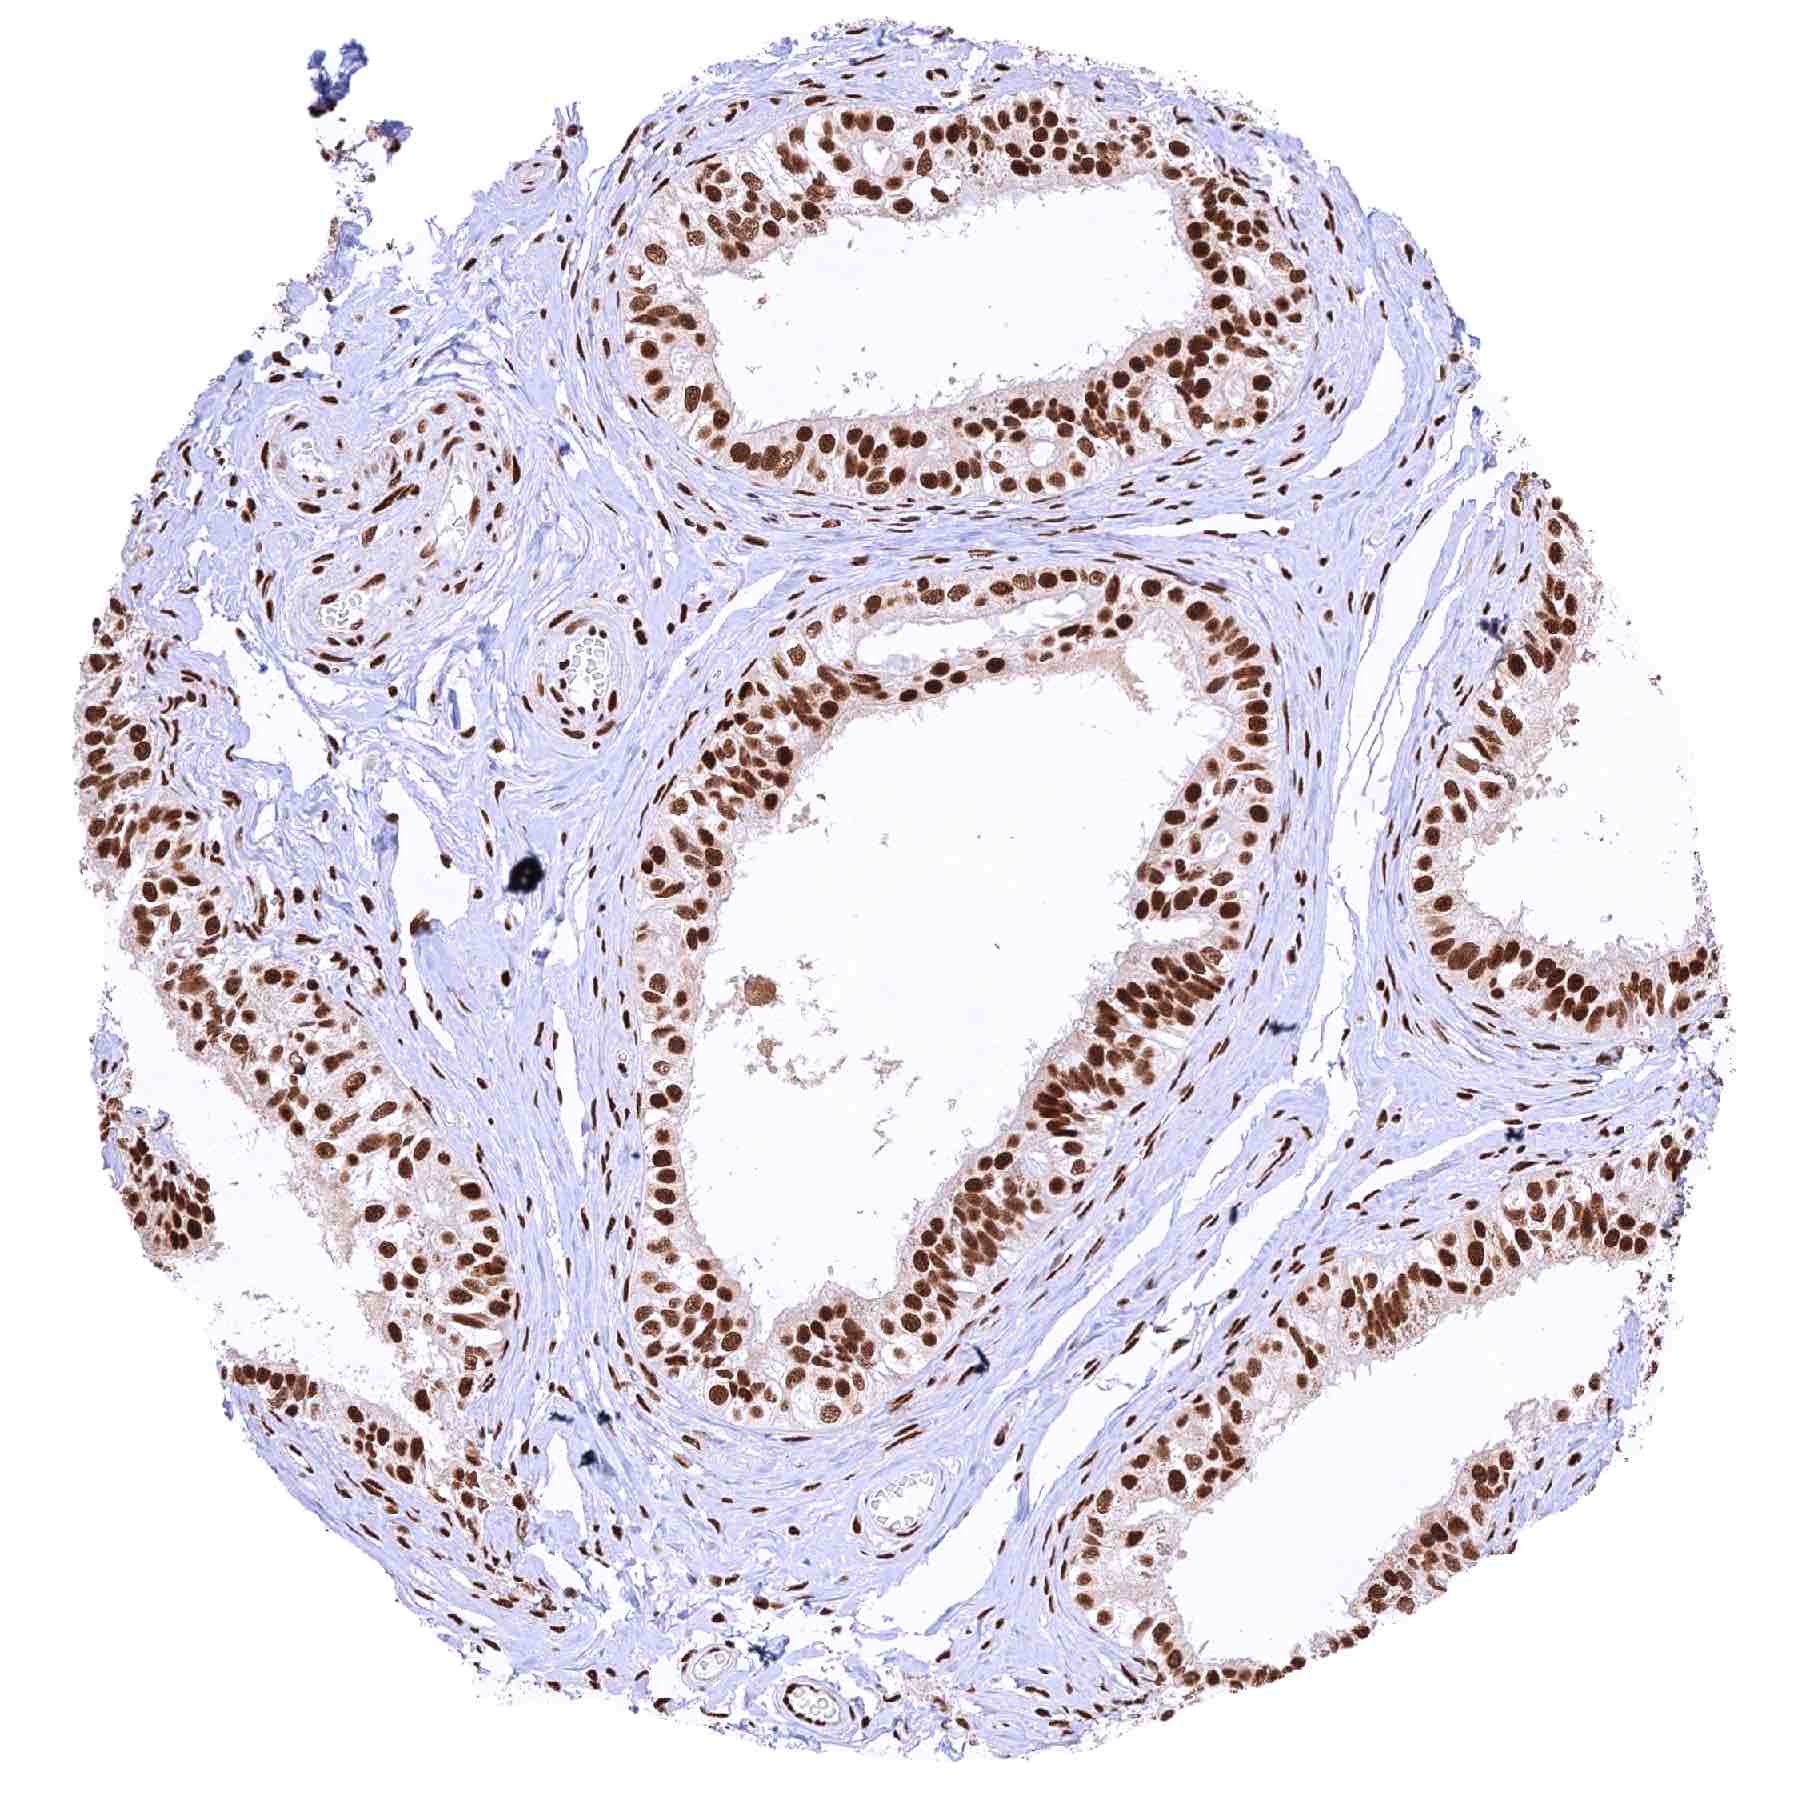

Esophagus, squamous epithelium – Slight but significant decrease of MRE11 staining from the basal-suprabasal to the superficial cell layers of the squamous epithelium